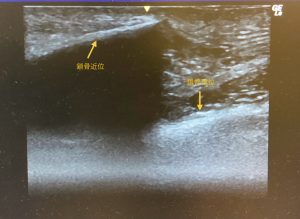

左鎖骨部(健側)

右鎖骨部骨折部エコー画像